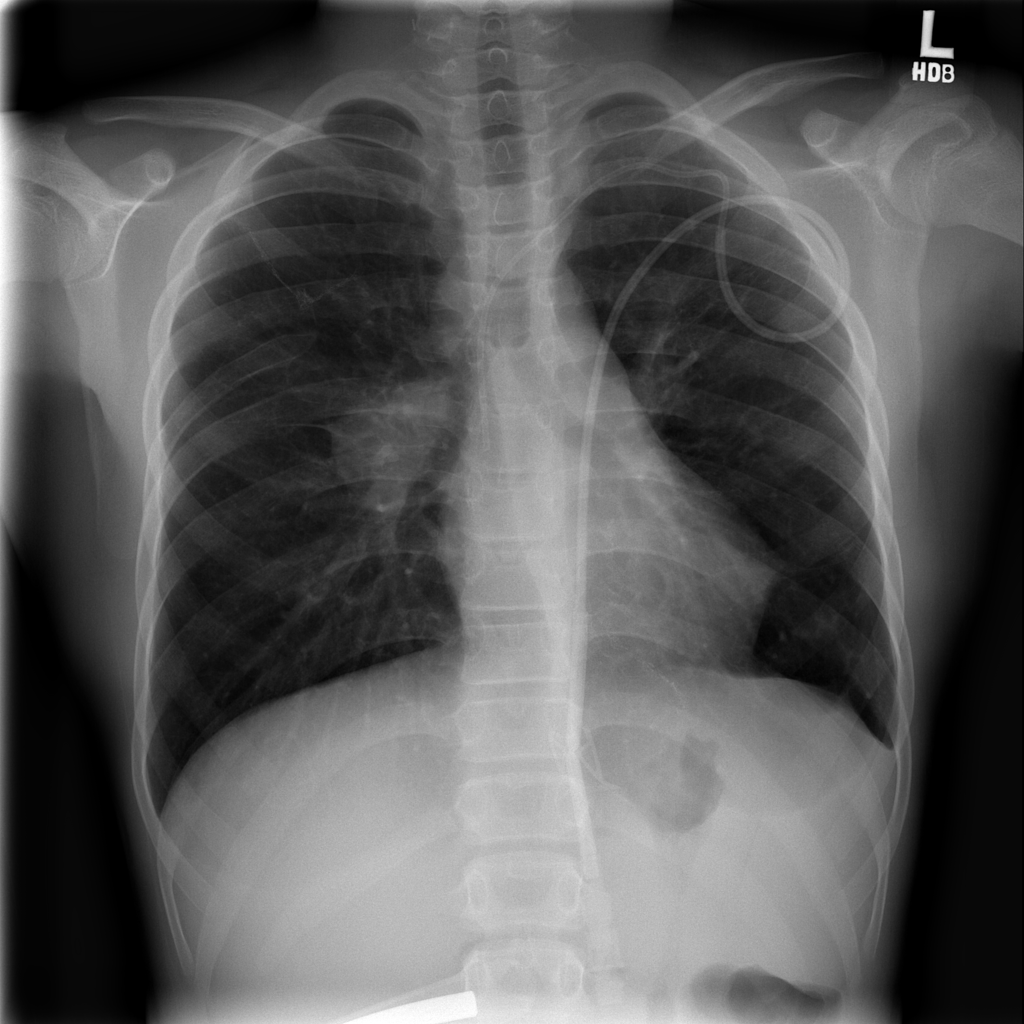

PAT-50E5 · IMG-008Mass

PAT-50E5 · IMG-008

PA